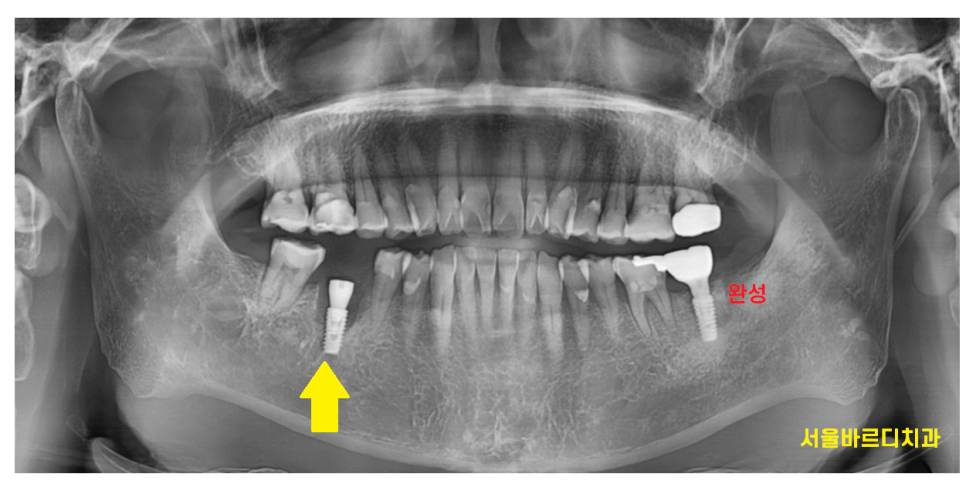

230130

왼쪽 아래 치아가 너무 아파서

도저히 못참겠다고 하셨습니다.

부러진지는 한참 됐는데

진통제를 먹으면서 참으셨답니다.

부러진 부위는

까맣게 변했을정도로 상태가 안좋았습니다.

외관상의 문제보다

뿌러지고 방치 되면서

치아 주변 뼈가 녹은게 관찰됩니다.

통증이 있는 상태라

해결을 위해서는 치아를 뽑아야 했는데요.

230214

아픈 왼쪽 아래 부위는

발치한 당일에 하남 미사 치과에서

임플란트를 심어 드렸습니다.